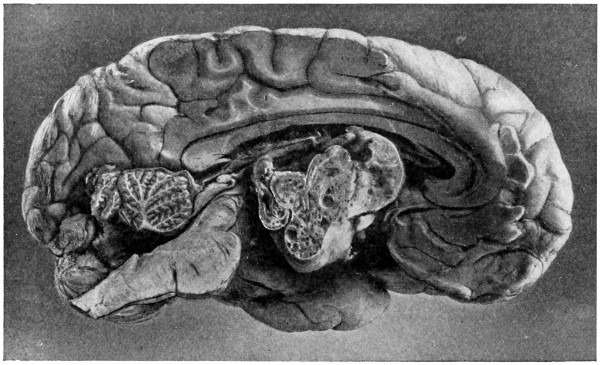

The child was 3 months old, and presented a tumour, the size of an orange, situated between the occipital protuberance and the nape of the neck. The mass was pedunculated, the stalk being about the size of a four-shilling piece in diameter. It was soft, translucent, irreducible, and swelled up on coughing. An attempt at removal was carried out, and, after incising the outermost layers, three ounces of cerebro-spinal fluid escaped. A second tumour was then found occupying the base of the swelling. This was also punctured, more fluid escaping. Both sacs were cut away and the wound sewn up. Death occurred on the third day, preceded by convulsions, retraction of the head and neck, and high fever. The autopsy showed that the fontanelles were widely open, the anterior measuring 4 inches from side to side and 212 from before backwards. The bones of the vault were markedly thinned. In the subdural space there was a quantity of fluid, and the cerebral substance was soft and diffluent, the convolutions flattened, and the ventricles distended. There was a broad gap in the occipital bone, extending downwards into the foramen magnum, and in this situation the cerebellum had bulged backwards into the protruding mass. (See Fig. 22).